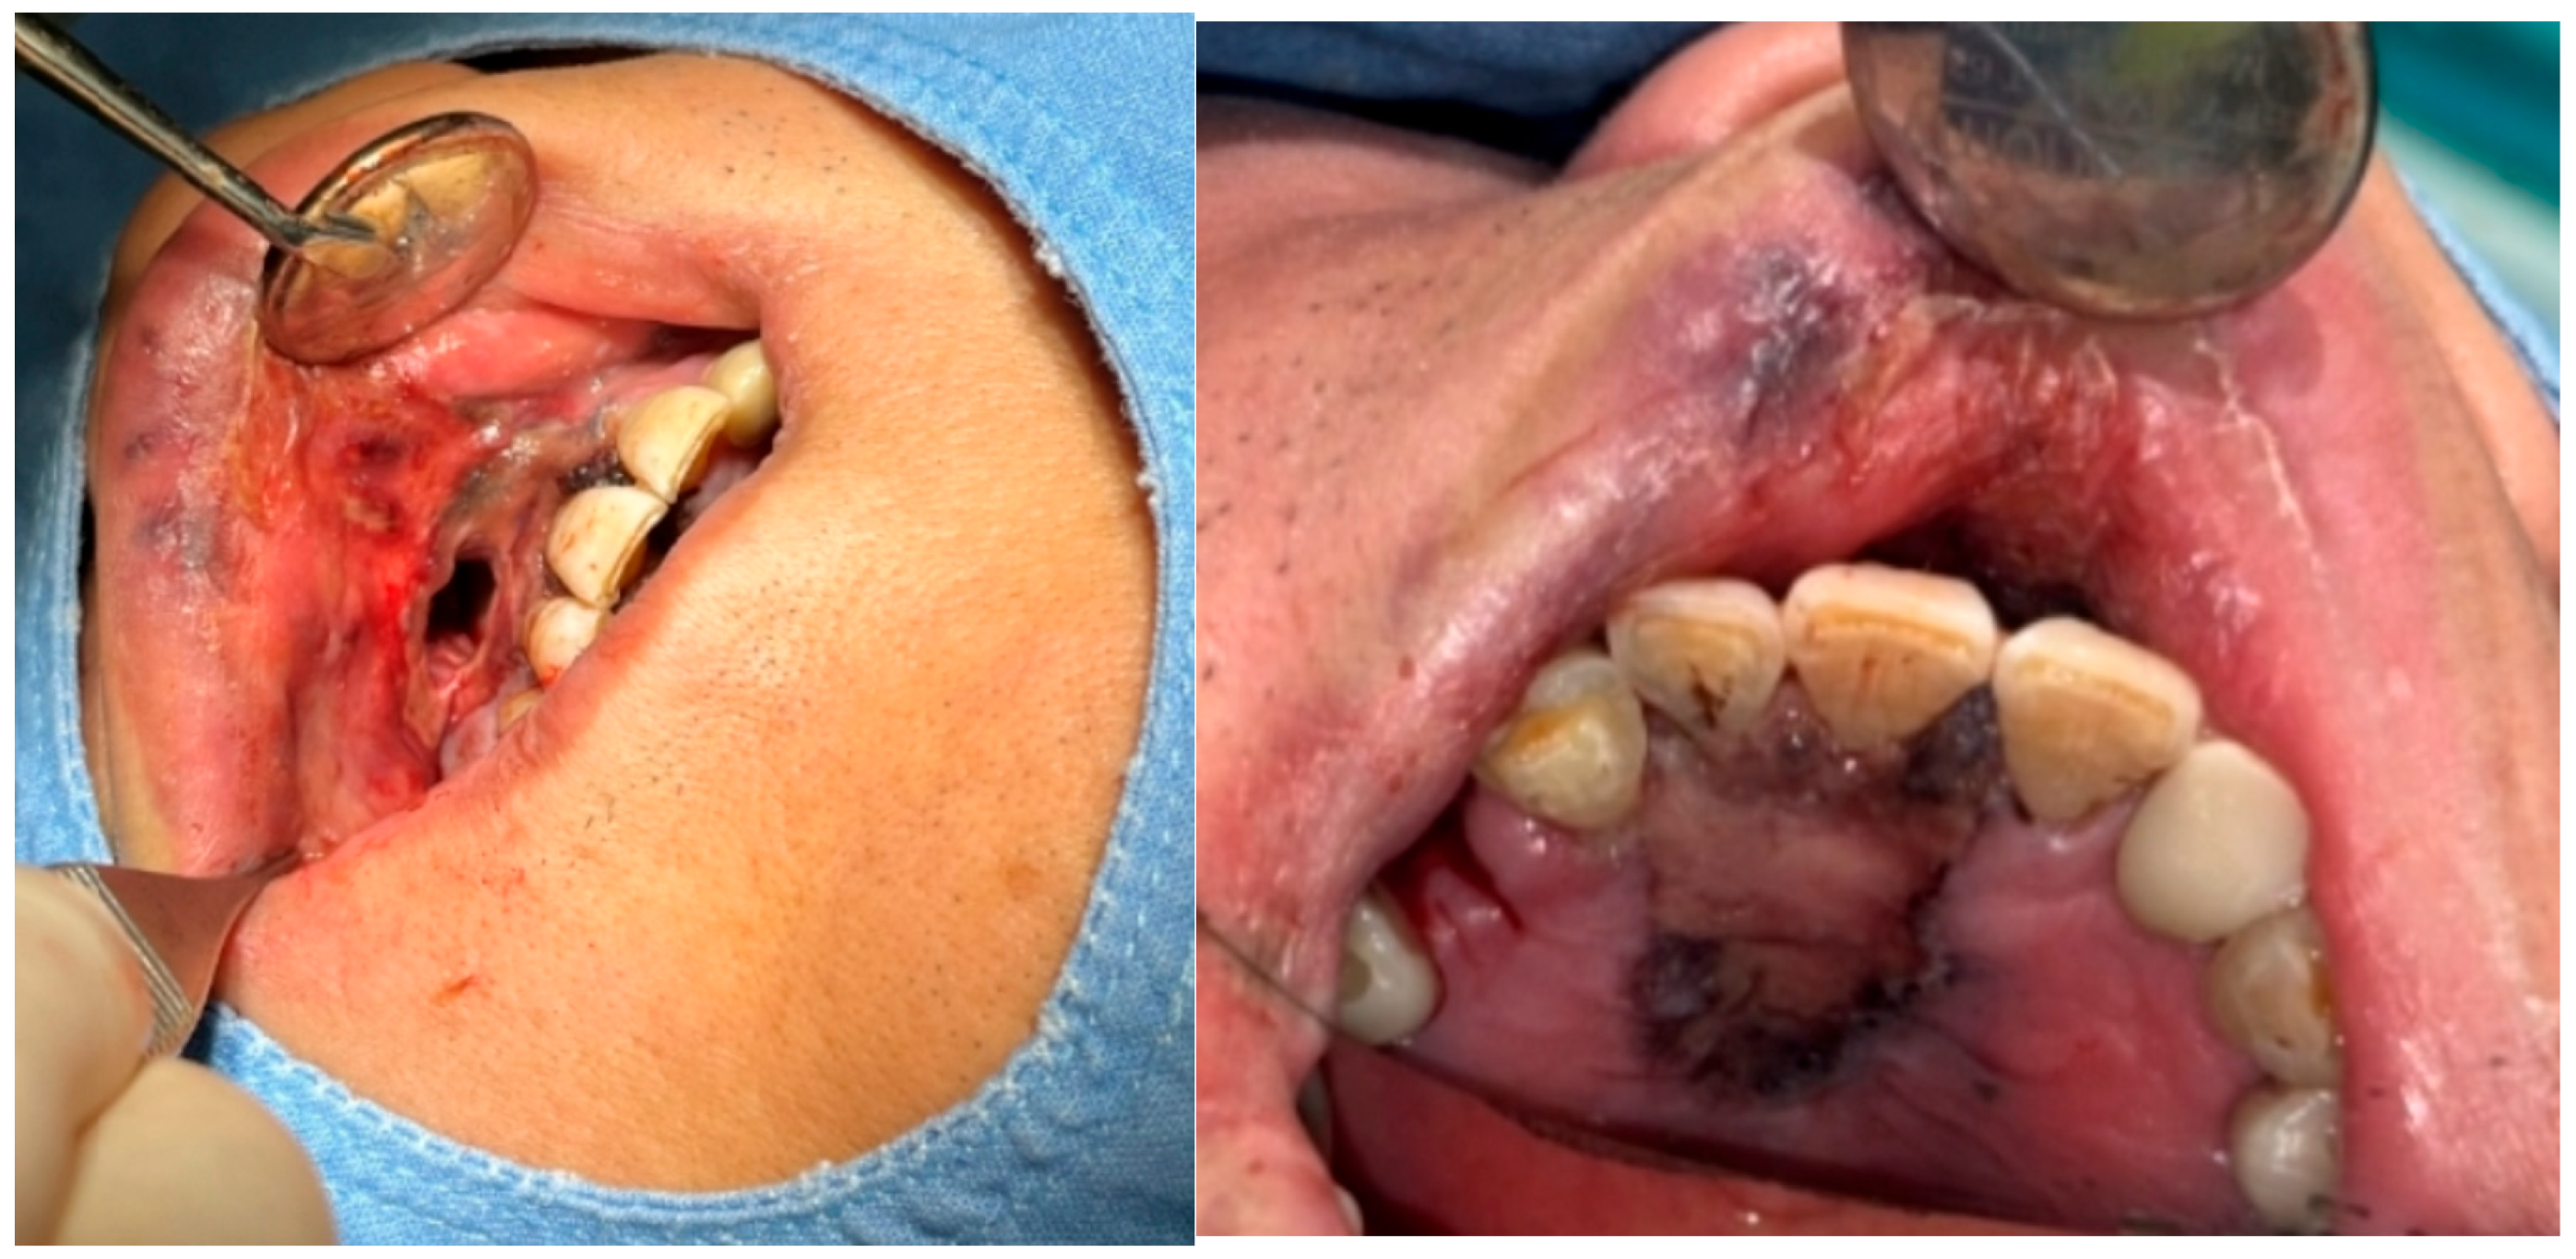

A 69-year-old male patient presenting with severe toothache 10 days before admission and melena 3 days before admission was admitted to the Infectious Disease Department of Kyung Hee University Hospital in the Republic of Korea in March 2025. The patient reported worsening toothache in the right upper gingiva with right facial swelling that began 5 days after a dental implant surgery at the upper right first premolar. Subsequently, the patient underwent incision and drainage at a local dental clinic one day before admission because of periodontitis that had spread to the facial area, as confirmed through the patient’s medical history. The patient had diabetes and was taking hypoglycemic agents. He had undergone coronary artery bypass grafting (CABG) for myocardial infarction 13 years previously. Additionally, he had undergone a prostatectomy for prostate cancer 2 years ago. He had been continuously taking clopidogrel (an antiplatelet agent) since undergoing CABG. The right buccal area of the face was swollen. Dental examination revealed a space abscess around the upper right first premolar (Figure 1). Panoramic dental X-ray showed that the implant fixture was placed in the alveolar bone of the upper right first premolar, and the external part has been removed (Figure 2). The implant fixture at the upper right first premolar was removed and irrigation and drainage were performed at the upper right first premolar and the vestibular area of the upper right second incisor, canine, and first premolar. The initial vital signs were blood pressure, 124/73 mmHg; pulse rate, 87 beats/min; respiratory rate, 20 breaths/min; temperature, 36.5 °C, oxygen saturation level, 98% on room air. Laboratory examination revealed a white blood cell (WBC) count of 6.23 × 109/L (83.0% neutrophils) and a C-reactive protein (CRP) level of 417.0 nmol/L. The aspartate aminotransferase, alanine aminotransferase, and alkaline phosphatase levels were 46, 57, and 97 IU/L, respectively. The serum creatinine level was 1.08 mg/dL and the BUN was 40 mg/dL. The serum sodium level was 129 mEq/L. Plasma level of glycated hemoglobin was 13.5%. Chest computed tomography revealed a mass-like lesion in the left lung with multiple small nodules in both lungs. Two sets of blood cultures were performed on the day of admission using BD Bactec Plus Aerobic/F and BD Bactec Plus Anaerobic/F bottles and a Bactec FX Instrument (Becton Dickinson, Sparks, MD, USA). The patient underwent esophagogastroscopy, which revealed active bleeding from multiple duodenal ulcers and subsequently received hemostatic treatment. A gastrointestinal bleeding dynamic computed tomography (CT) scan showed a liver abscess at S2/3 (3.1 cm) (Figure 3a) with focal septic thromboembolism in the left hepatic vein (Figure 3b). Chest CT revealed mass-like consolidation and air densities in the left upper and lower lobes, along with multiple irregular nodules with ground-glass opacities in both lungs (Figure 3c,d).

Figure 2. Initial panoramic dental X-ray. The implant fixture is placed in the alveolar bone of the upper right first premolar, and the external part has been removed.